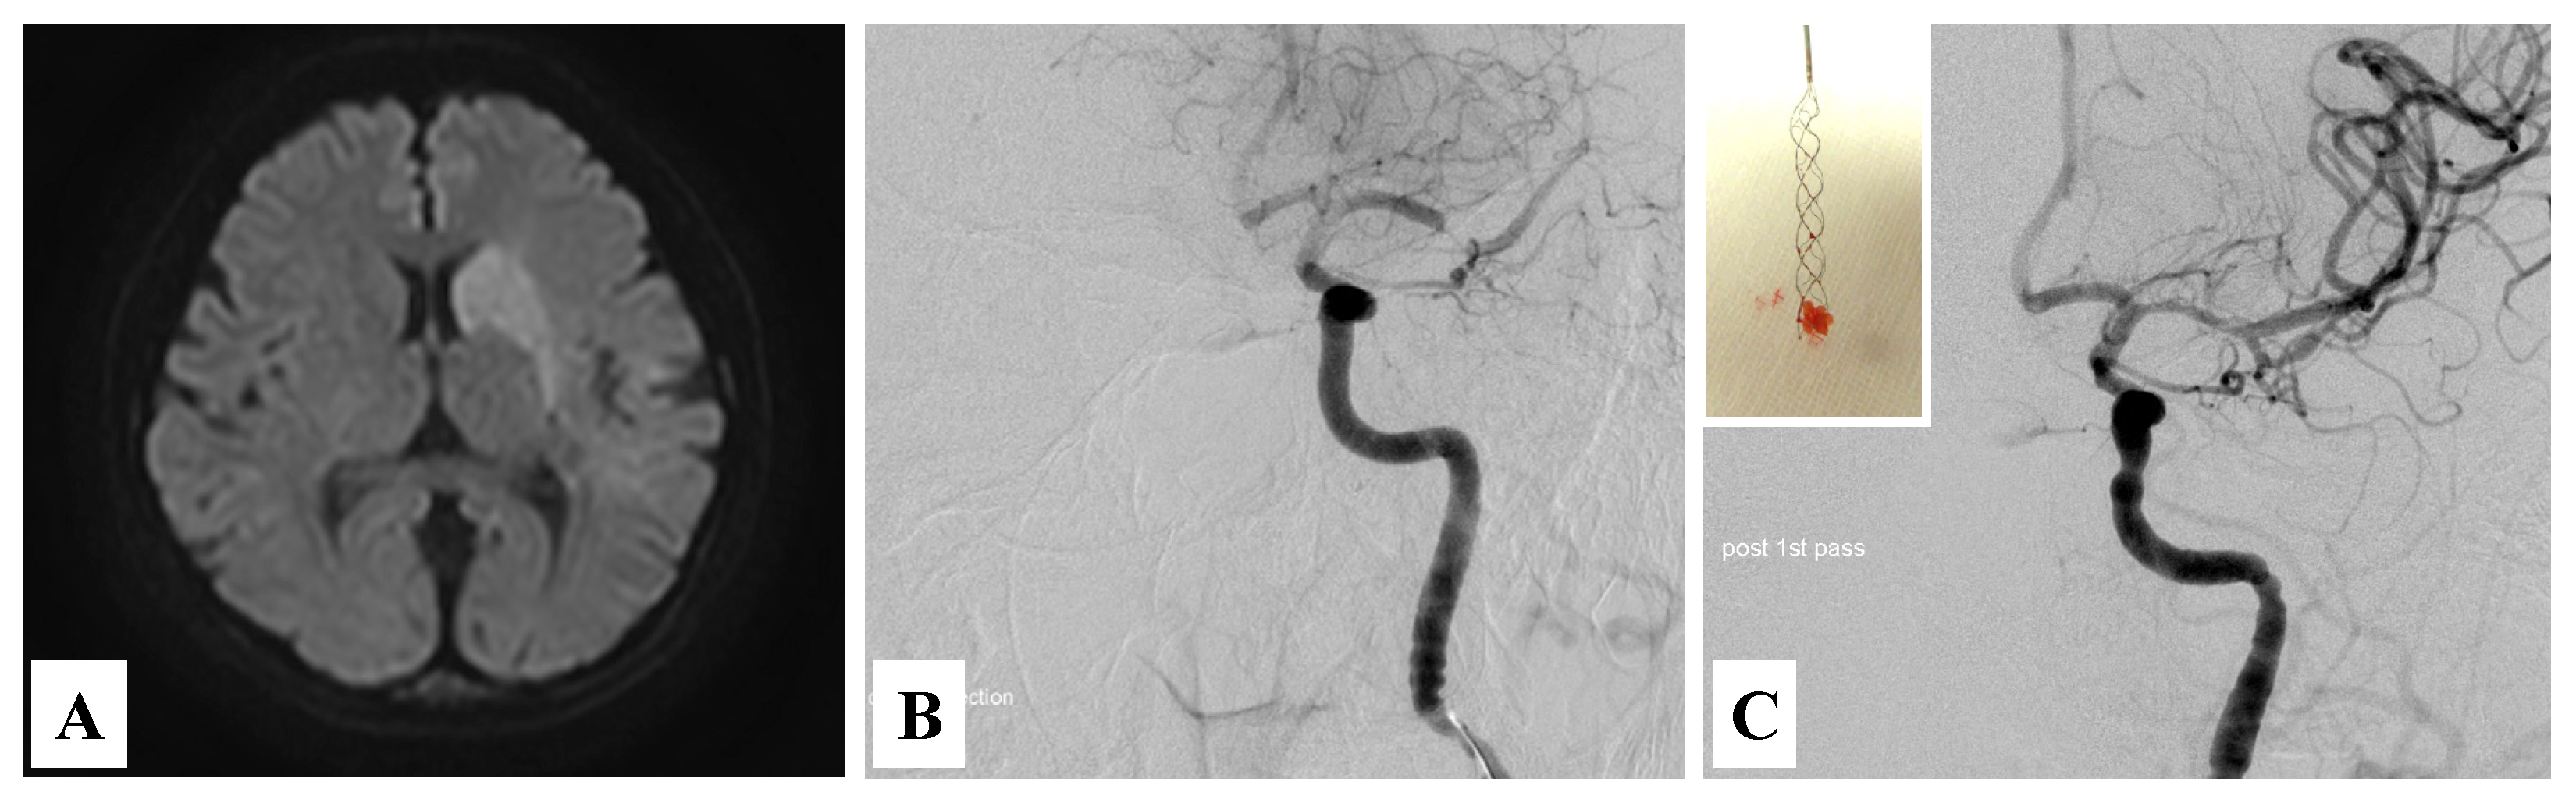

2. Case Presentation